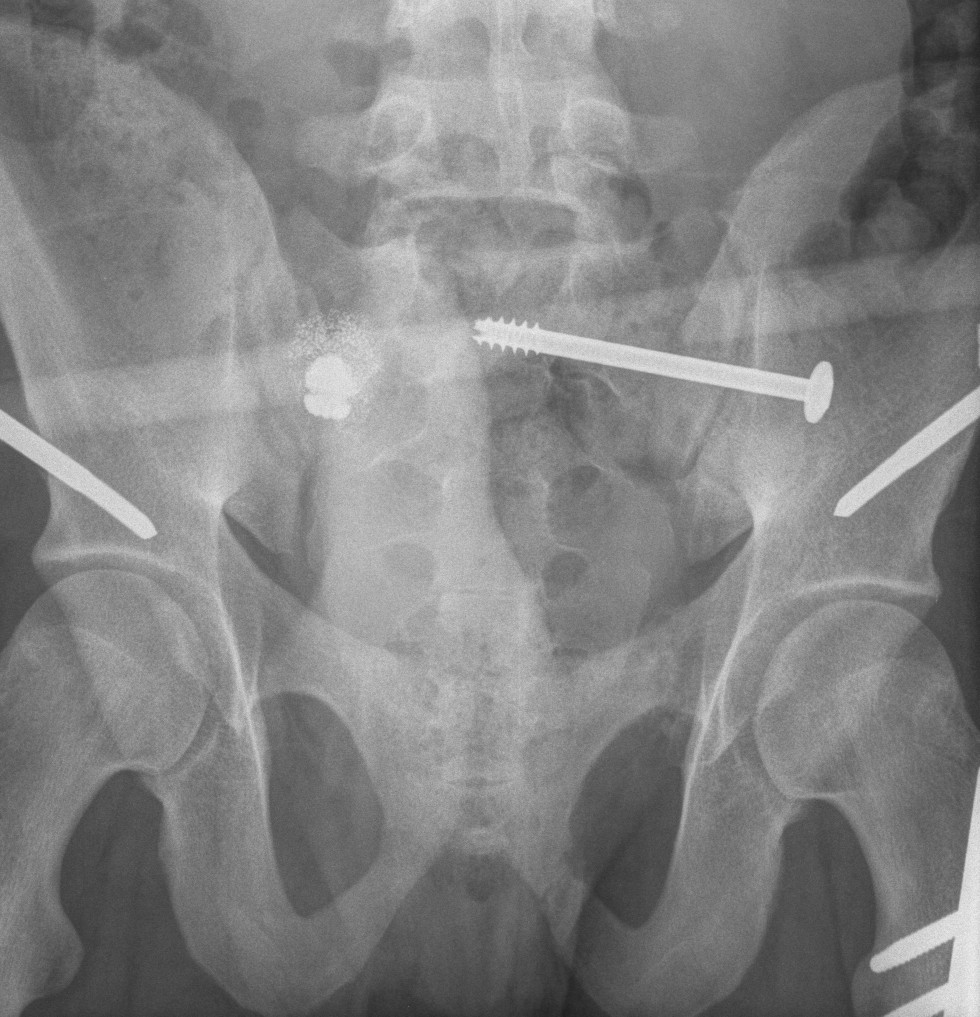

Guide wire insertion into body of S1

- anatomic safe zone

- between S1 foramen and superior ala on outlet view (outlet view)

- between neural canal and anterior body (inlet view)

Insert 6.5 mm partially threaded cannulated screw, to aid compression

Post operative

Check screw position with CT